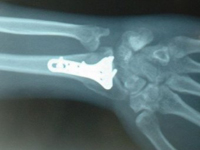

Швейцарские ученые разработали и успешно испытали на животных новый материал, который может существенно облегчить лечение сложных переломов. Исследователи предлагают использовать для изготовления спиц, шурупов и других видов креплений для костей прозрачный сплав магния, цинка и кальция.

Новый материал достаточно прочен и гибок для того, чтобы выдержать нагрузку на кость. При этом он способен медленно растворяться в организме пациента без каких-либо токсических эффектов.

В настоящее время при лечении переломов используются импланты из нержавеющей стали и титана. Такие крепления со временем изнашиваются и деформируются, в результате чего достаточно часто возникает необходимость в повторных хирургических вмешательствах. Перспективной альтернативой стальным и титановым креплениям являются крепления из биорастворимых материалов, в частности – из сплавов магния.

Незначительные количества магния, цинка и других металлов, поступающие в организм при медленном растворении такого материала, не представляют опасности для организма и быстро выводятся из него. Однако обычно этот процесс сопровождается химической реакцией с выделением свободного водорода, который может повредить живые ткани.

Группе ученых из швейцарского Государственного технологического института Цюриха под руководством Йорга Лоффлера (Jörg Löffler) удалось преодолеть это препятствие с помощью особой техники быстрого охлаждения сплава, включающего 60 процентов магния, 35 процентов цинка и 5 процентов кальция. В результате структура кристаллической решетки сплава менялась, и выделения свободного водорода при его растворении жидких средах организма не происходило.

Исследователям также удалось показать, что скорость растворения полученного ими материала можно регулировать, меняя содержание в нем цинка. Это дает дополнительную возможность для регулирования продолжительности срока, в течении которого крепления разного назначения будут выполнять свою функцию. Биосовместимость и безопасность нового материала подтверждена опытами на животных. Однако, по признанию ученых, для того чтобы обосновать целесообразность его использования в медицине, потребуются дополнительные лабораторные эксперименты.